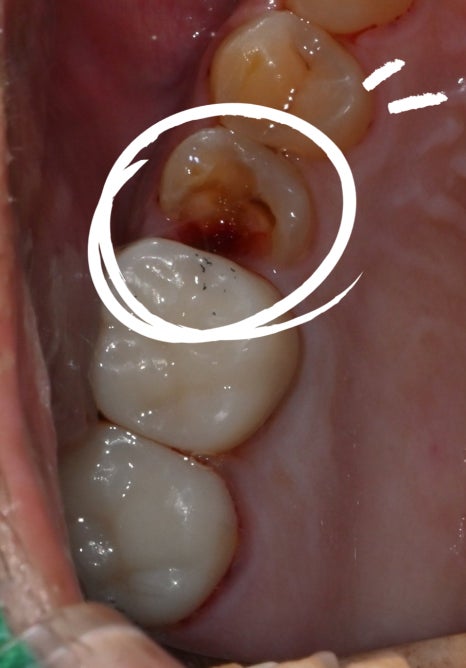

At the initial visit

The right tooth broke, and it feels sensitive and painful.

After checking the X-ray, we found that the cavity was so severe that the tooth

had come in broken.

When a molar breaks like this,

root canal treatment is necessary.

<Before treatment / After treatment>